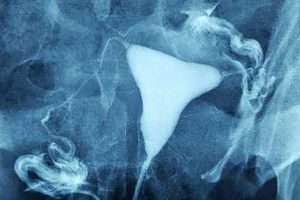

Normal HSG

Normal HSG Filmi